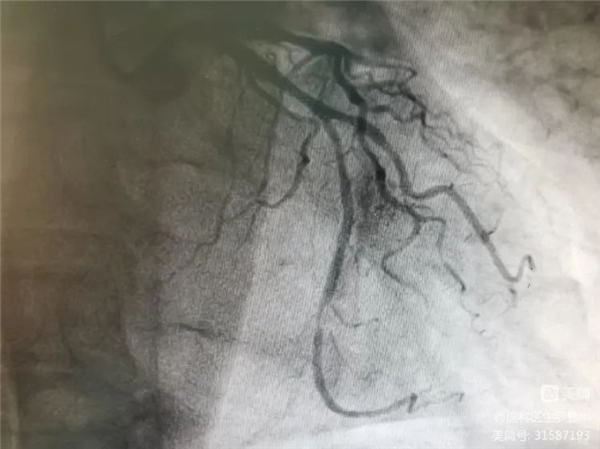

冠脈造影證實左旋支重度狹窄

沈桂冬主任團隊正在為患者行PCI術